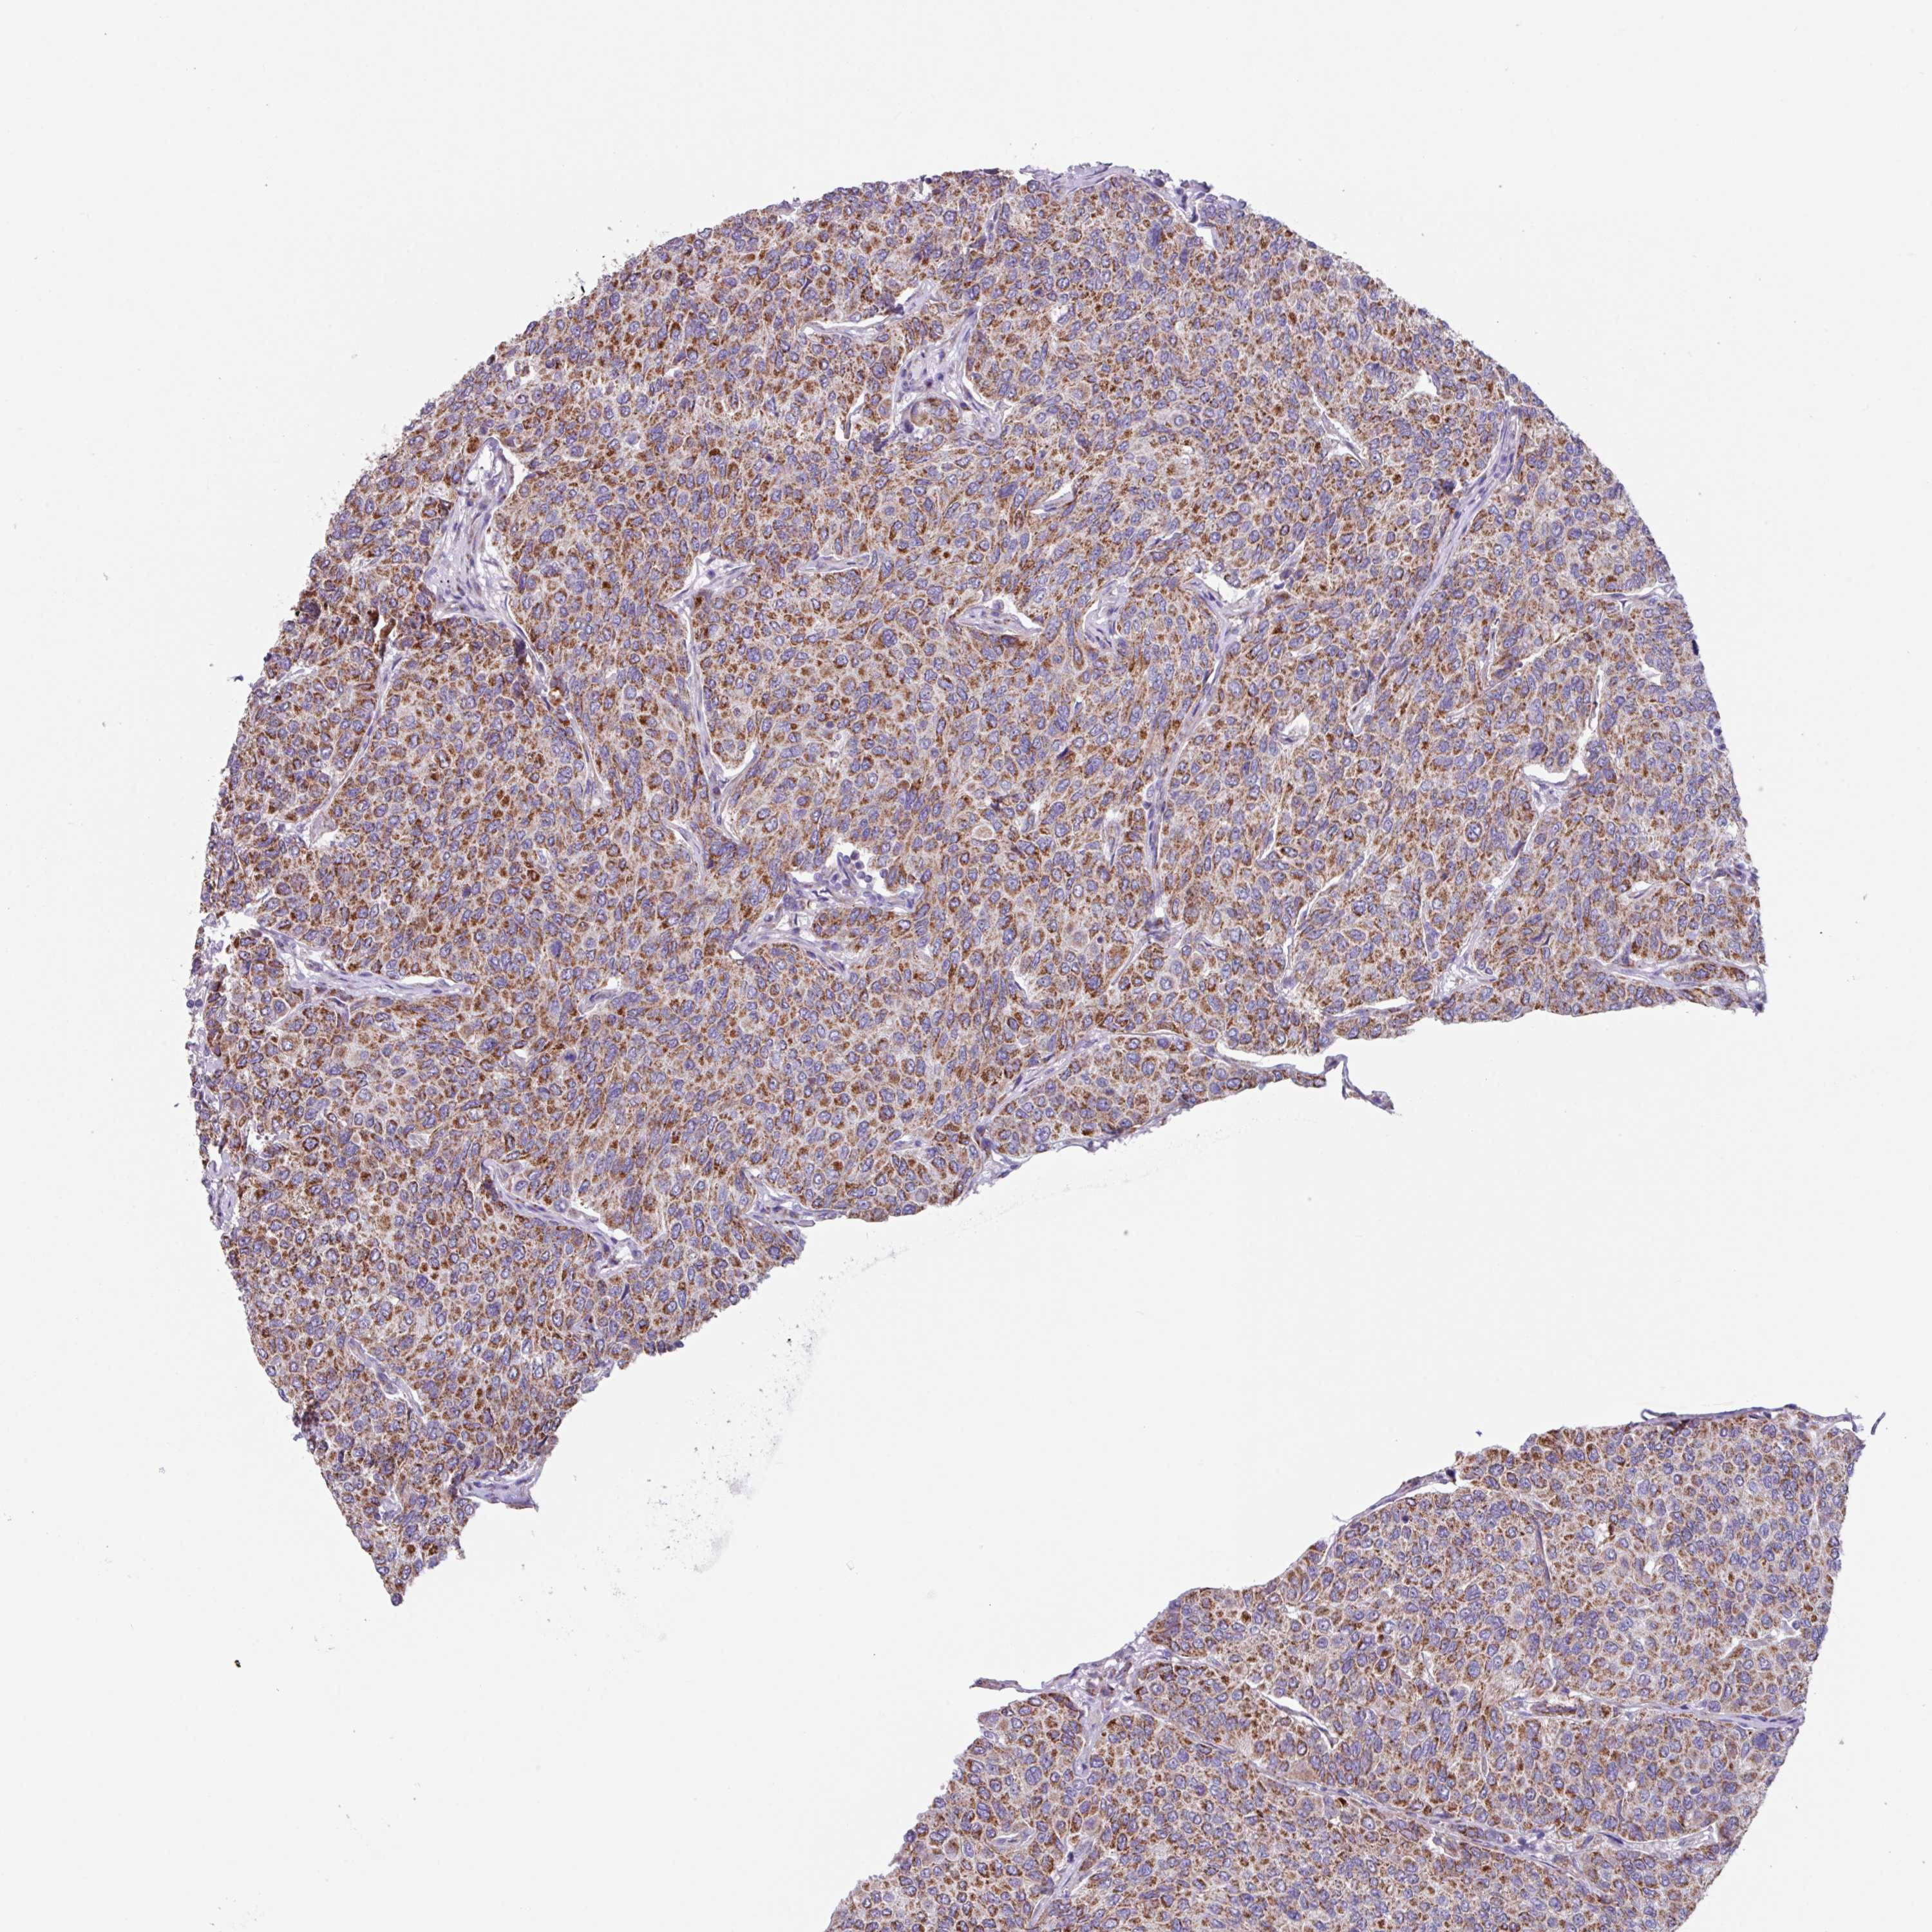

CANCER BREAST CANCER Show tissue menu

BRCA TCGA BRCA VALIDATION PROTEIN EXPRESSION

Breast cancer

Human cancer